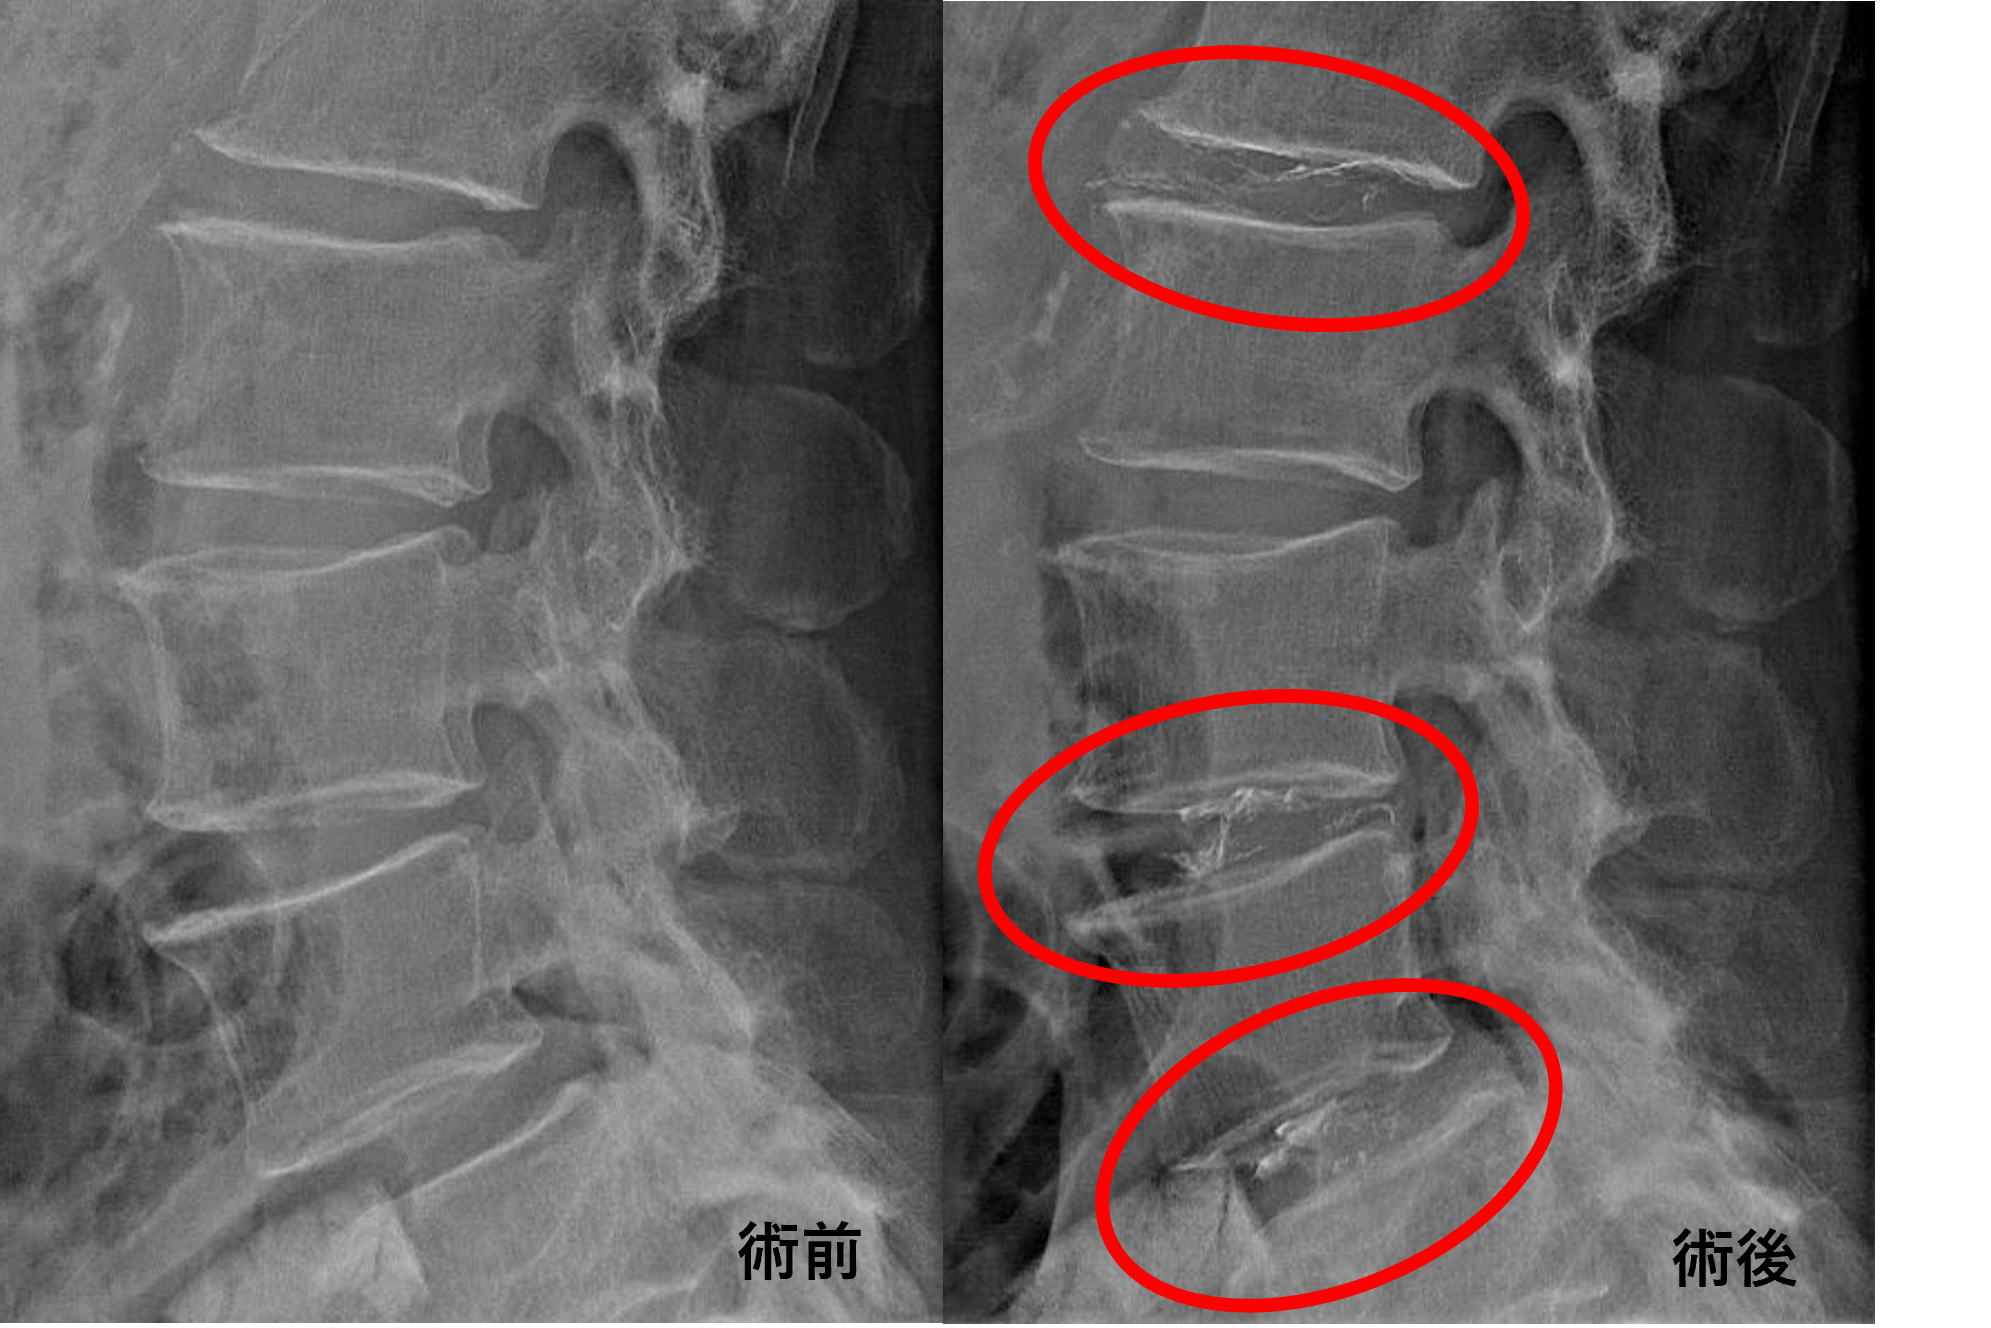

画像及び所見について

- L1/2、3/4、4/5 – 椎間板変性、膨隆、椎間孔狭窄

- L2/3、5/s – 椎間板変性、膨隆

以上のことが画像上認められました。

L1/2、3/4、4/5の椎間板所見による脊柱管の圧排が、症状の原因の可能性がもっとも高い。

患者様と相談の元、L1/2、3/4、4/5にセルゲル法を施行